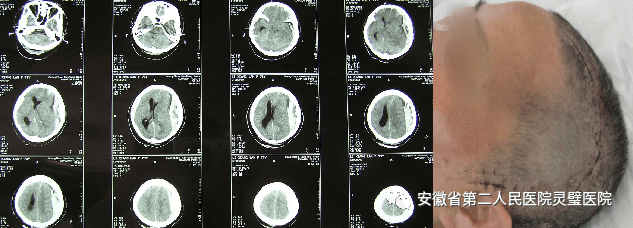

四、脑出血的综合治疗技术

脑出血是临床常见神经重症,原发性高血压是最常见原因之一,根据病人的不同特点,我科形成了从保守治疗、微创治疗到去大骨瓣减压等系列个性化特色技术,临床救治水平达到国内先进水平。

经额穿刺血肿引流术

经颞小骨窗神经内镜下血肿清除术

去大骨瓣减压术+脑内血肿清除术